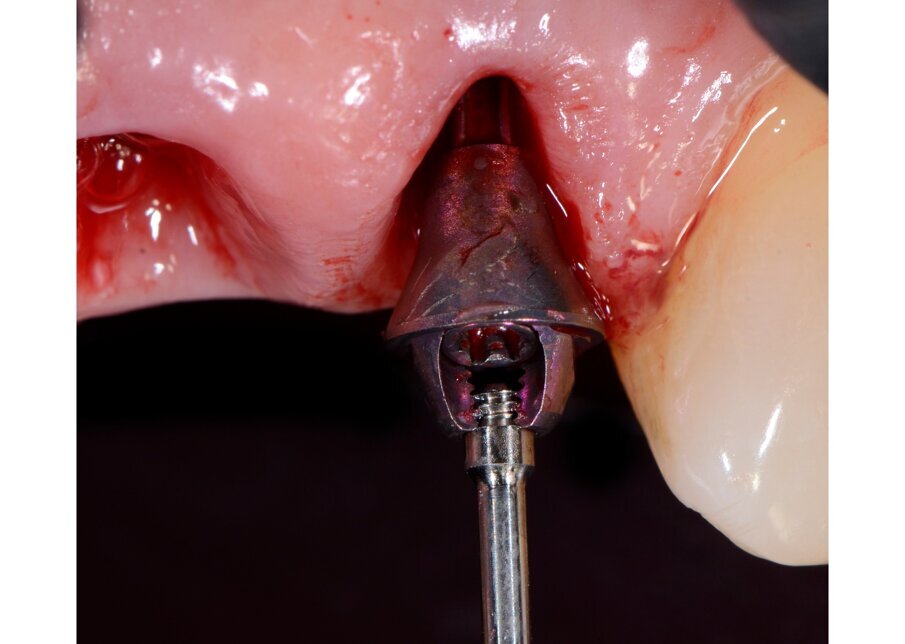

Il nostro obiettivo è quello di riuscire a dare alla paziente un provvisorio immediato nell’arco di due ore. Questo diventa possibile perché abbiamo utilizzato un flusso digitale fin dall’inizio. In laboratorio vengono realizzate la dima chirurgica (Figg. 16, 17), la dima protesica (Fig. 18) e anche il provvisorio (Figg. 19-21) che contiene delle alette di riposizionamento. Il tutto gestito con modelli digitali sui quali saremo in grado di funzionalizzare il provvisorio post-chirurgico (tecnica DIL). In un caso come questo se utilizziamo un flusso digitale possiamo evitare subito dopo la chirurgia di rilevare un’impronta degli impianti inseriti. Infatti, utilizziamo una dima chirurgica che ci faciliterà le fasi di intervento. La dima ci consentirà di non fare lembi e nessuna incisione di rilascio (Fig. 22), dopo aver inserito gli impianti (BLX Straumann) (Figg. 23-31) e aver controllato il loro alloggiamento, inseriamo sugli stessi dei transfert da impronta (Fig. 32).

Fig. 25 - Preparazione letto implantare.

Fig. 26 - Impianto BLX Straumann.

Fig. 27 - Posizionamento impianto 1.2.

Fig. 28 - Alloggiamento finale.

Fig. 29 - Posizionamento impianto 2.2.

Fig. 30 - Alloggiamento finale.

Fig. 31 - Visione occlusale impianti inseriti.

Fig. 32 - Transfert avvitati sugli impianti.

Alloggiamo la dima protesica (Fig. 33), e blocchiamo i transfert con della resina trasparente (tecnica DIL) (Figg. 34, 35). In questo modo possiamo far riposare il paziente in studio dopo appena 35 minuti dall’inizio dell’intervento. La dima protesica, infatti (Fig. 36) con i transfert inseriti viene completata con l’unione degli analoghi ai transfert (Fig. 37). L’insieme così composto viene riadattato sul modello master digitale iniziale (Figg. 38-40) sul quale era stata costruita sia la dima chirurgica che la dima protesica come anche il provvisorio. Gli analoghi vengono bloccati sul modello con resina trasparente (Figg. 41-43). Alloggiamo il provvisorio sul modello master digitale così ottenuto (Figg. 44, 45).